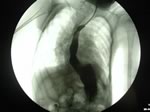

- Deglutogramma e transito esofageo con pasto di bario: evidenzia il passaggio del bolo di mezzo di contrasto dall’orofaringe allo stomaco, e l’eventuale reflusso (Figura 2), mettendo in luce anche alterazioni anatomiche (ernia iatale). Offre inoltre la possibilità di studiare il transito oltre il piloro. Il difetto dell’esame è quello di “fotografare” ciò che accade in “quel momento”, ed in questo senso la sensibilità per RGE è di fatto stimata intorno 50%. Nei bambini portatori di gastrostomia percutanea per via endoscopica (PEG) il contrasto è iniettabile attraverso il “bottone” di gastrostomia (Figura 2 bis).